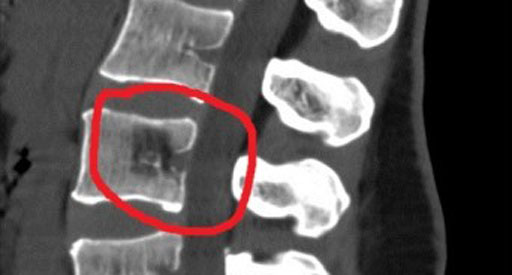

Благодаря высокой эффективности чрескожная вертебропластика часто применяется при симптоматичных опухолях тел позвонков. К таким опухолям относятся доброкачественные гемангиомы и злокачественные миеломные болезни. Показаниями к операции также являются «критический» остеопороз позвоночника, единичные метастазы рака в телах позвонков (в пределах пораженного участка), а также травматические повреждения с болевым синдромом, такие как компрессионные переломы тел позвонков I–II степени и риск их возникновения, а также посттравматический остеонекроз (болезнь Кюммеля).

Перед хирургическими вмешательствами необходимо провести полное обследование, включая МРТ или КТ спинного мозга, а также консультацию у невролога. Для снижения вероятности осложнений назначаются антибиотики из группы цефалоспоринов, которые следует вводить за 12 часов до операции. Накануне вмешательства, начиная с 19:00, пациенту назначается диетический стол №0, при этом употребление воды также запрещено.

После процедуры в течение первых 20 минут пациенту нельзя двигаться, он должен соблюдать постельный режим в течение 2 часов. Для уменьшения болевых ощущений врач назначает анальгетики в индивидуальной дозировке. Через 2–3 часа проводится контрольное КТ или рентгенография.